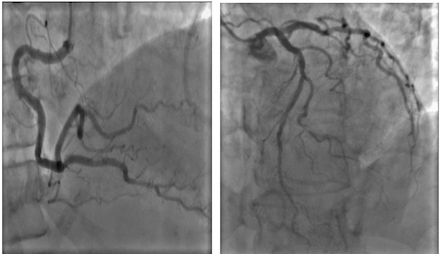

Case Discussion: A 71-year-old postmenopausal woman presented with acute dyspnea and elevated troponin (2900 pg/mL). Her history included traumatic SAH three months prior with a normal echocardiogram at that time. Electrocardiogram showed non-specific T-wave changes . Transthoracic echocardiography revealed severe left ventricular dysfunction (ejection fraction 25-30%) with apical ballooning and mid-to-apical hypokinesis, consistent with TTS . Coronary angiography confirmed non-obstructive coronary arteries. No recent stressors or acute neurological events were identified, suggesting a delayed TTS linked to the prior SAH. Heart failure therapy was initiated; follow-up echocardiography is pending.